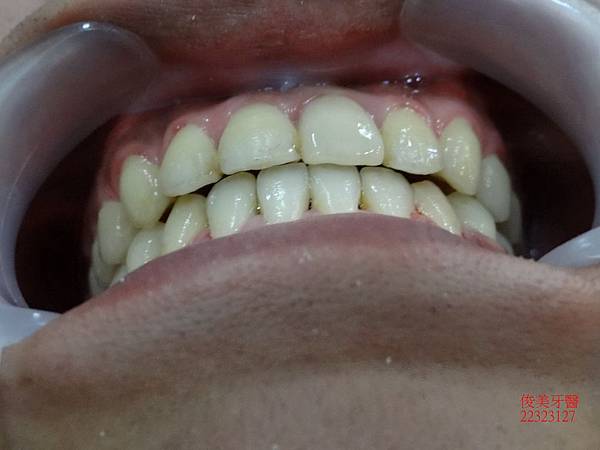

原始狀況~~

咬合狀況。

上排牙明顯被下排牙齒限制住。